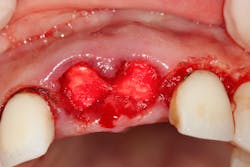

- Pack the socket with a hemostatic plug such as gel-foam, surgical, Avitene, collagen plug, or Helistat/HeliPlug (figure 2).